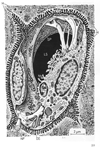

消化器;消化器系【しょうかきけい】(栄養分を取りこむ器官系で、言い換えれば、身体の成長に必要な物質と身体の活動を支えるためのエネルギー源とを取り入れるのが消化器の役割である。消化器は口腔・咽頭・食道・胃・小腸・大腸などから構成された「消化管」とこれに開く唾液腺・肝臓・膵臓などの「消化腺」とから出来ている。)